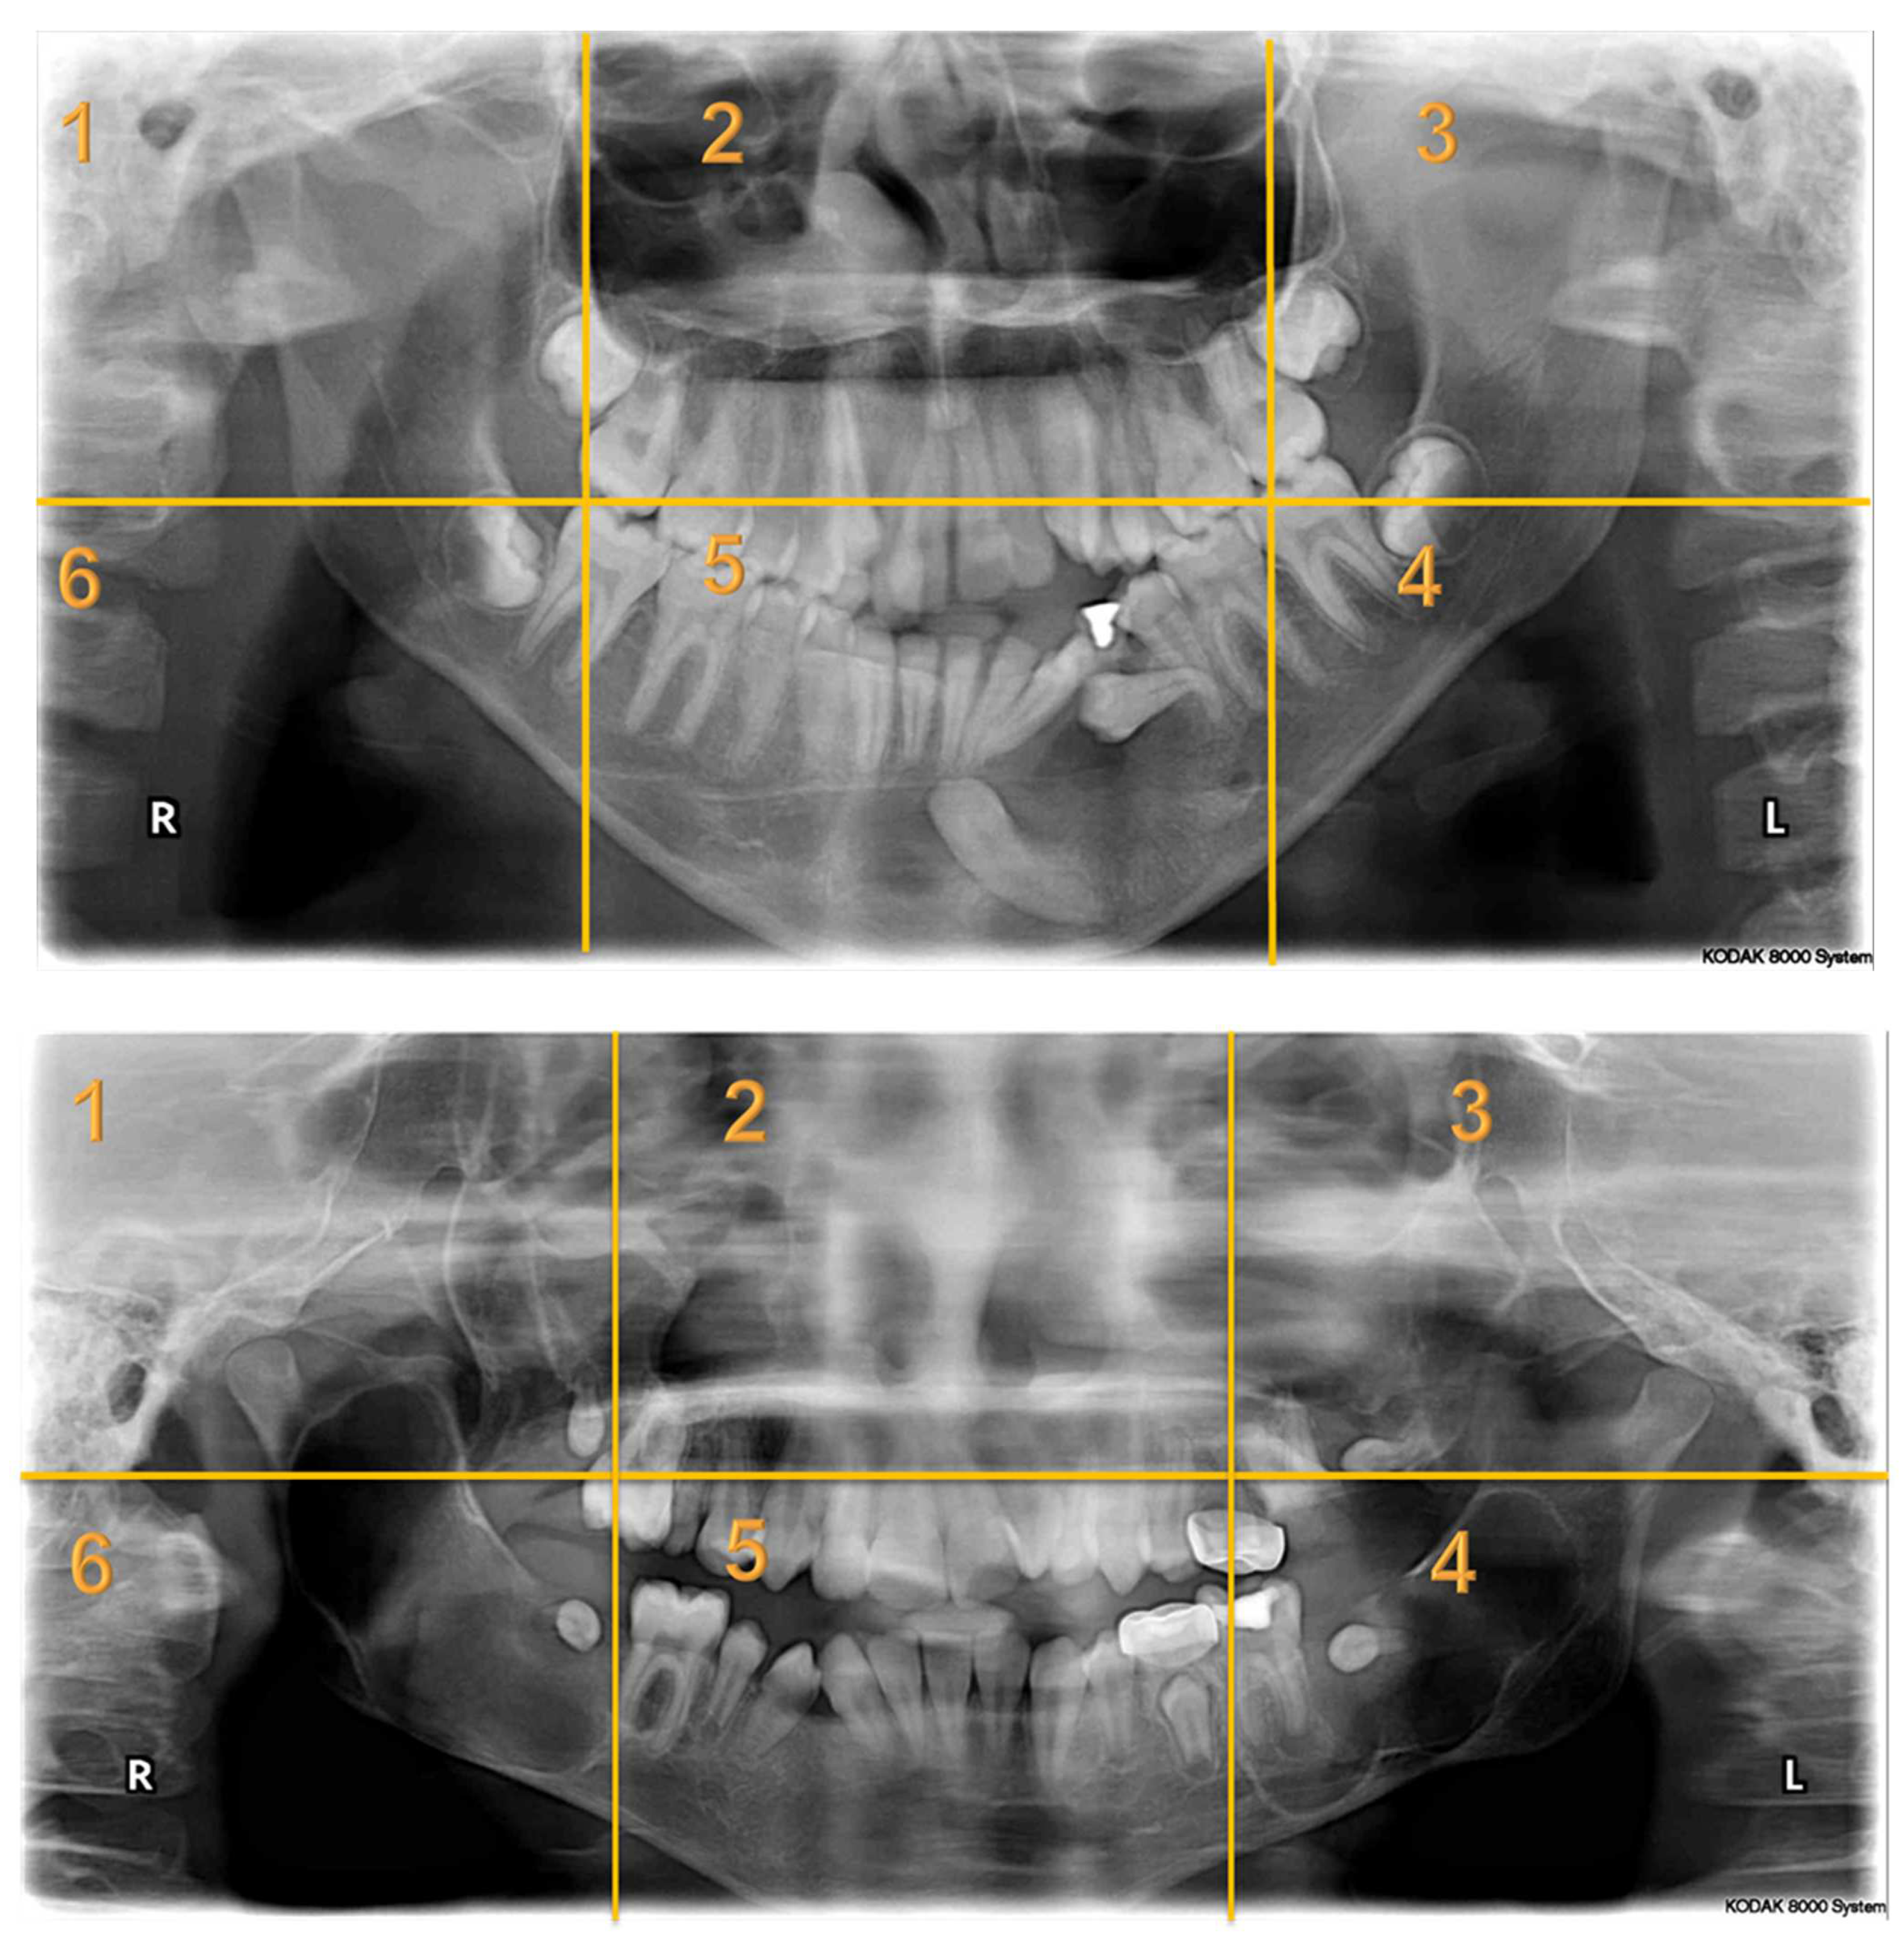

Seven panoramic radiographs (Appendix A) of pediatric dental patients aged between 6 and 16 years of age were selected from the electronic health system of KAUDH, based on their quality. Case selection mandated the presence of at least one bony lesion. A panel of experts from KAUDH, including three pediatric dentists and an oral radiologist, reviewed the selected cases to ensure that the radiographs were of good quality. All the images used in the study underwent no manipulation. The type of lesion was recorded for each patient and confirmed by their dental records. All identifying data were removed and a de-identified serial number was assigned to each case. The panoramic radiographs in this study presented a wide variety of abnormalities that included deviated nasal septum and enlarged nasal conchae; fibrous dysplasia; regional odontodysplasia or ghost teeth; dentigerous cysts; odontogenic keratocysts; enlarged dental follicle; missing, impacted, and rudimentary teeth; dilacerated roots; retained primary teeth; and periapical radiolucencies.

Appendix A. Radiographs Included in the Study